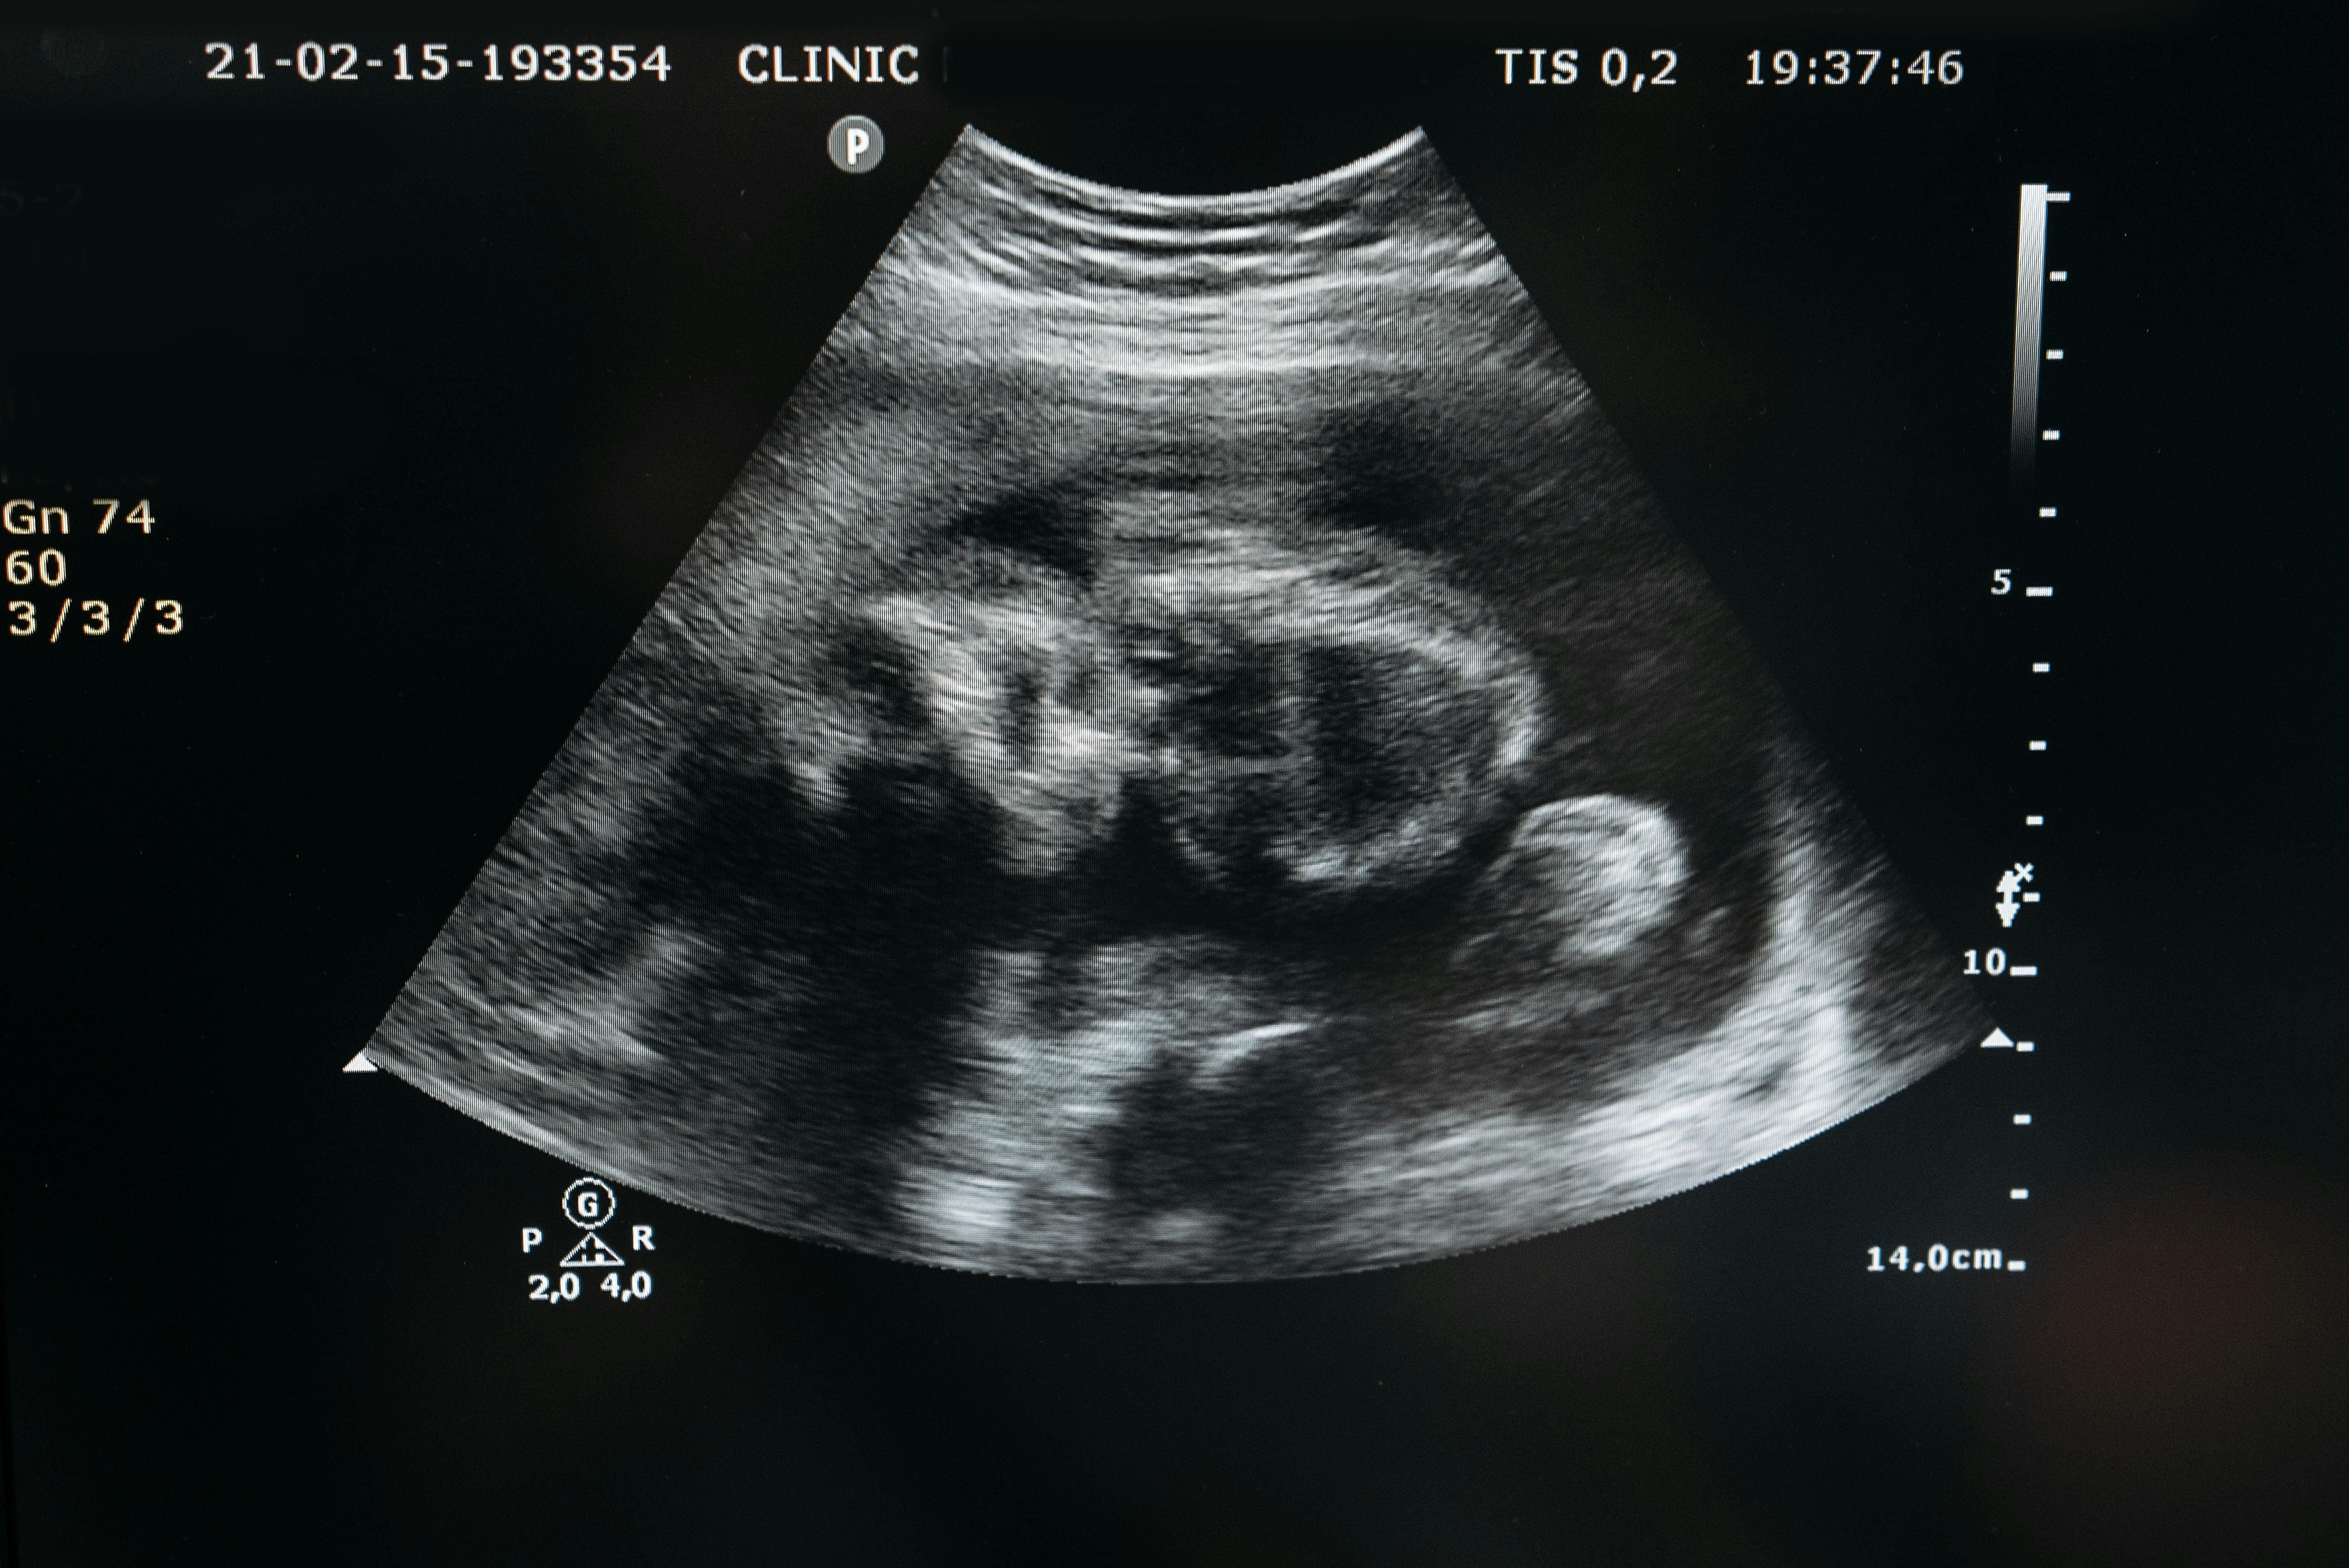

임신 기간 동안 많은 설렘과 기대를 느끼지만, 출산 진통에 대한 두려움도 함께 커지고 있으신가요? 😰 특히 첫 아이를 갖는 예비 엄마라면 이러한 걱정이 더 크실 거예요. 많은 산모들이 무통분만으로 통증을 줄이며 출산하고 있어요. 오늘은 출산을 앞둔 예비맘들을 위해 2025년 최신 무통분만 정보를 알아볼게요!

무통분만은 통증을 완전히 없애는 것이 아니라, 크게 줄여주는 방법이에요. 경막 외 마취가 가장 일반적이며, 산모와 아기 모두에게 안전한 것으로 입증되었습니다. 2025년 현재 초산모의 94% 이상이 선택할 정도로 보편화되었어요.

2025년 현재 무통분만, 특히 경막외 마취는 초산모의 94% 이상이 선택할 정도로 인기가 많아요. 이렇게 많은 산모들이 선택하는 이유, 즉 장점을 알아볼게요.

특히 고혈압, 당뇨, 임신중독증 등 고위험 임신이나 쌍둥이 출산의 경우 무통분만이 큰 도움이 될 수 있어요. 심한 통증으로 인한 스트레스 호르몬이 이런 상태를 악화시킬 수 있기 때문이에요.